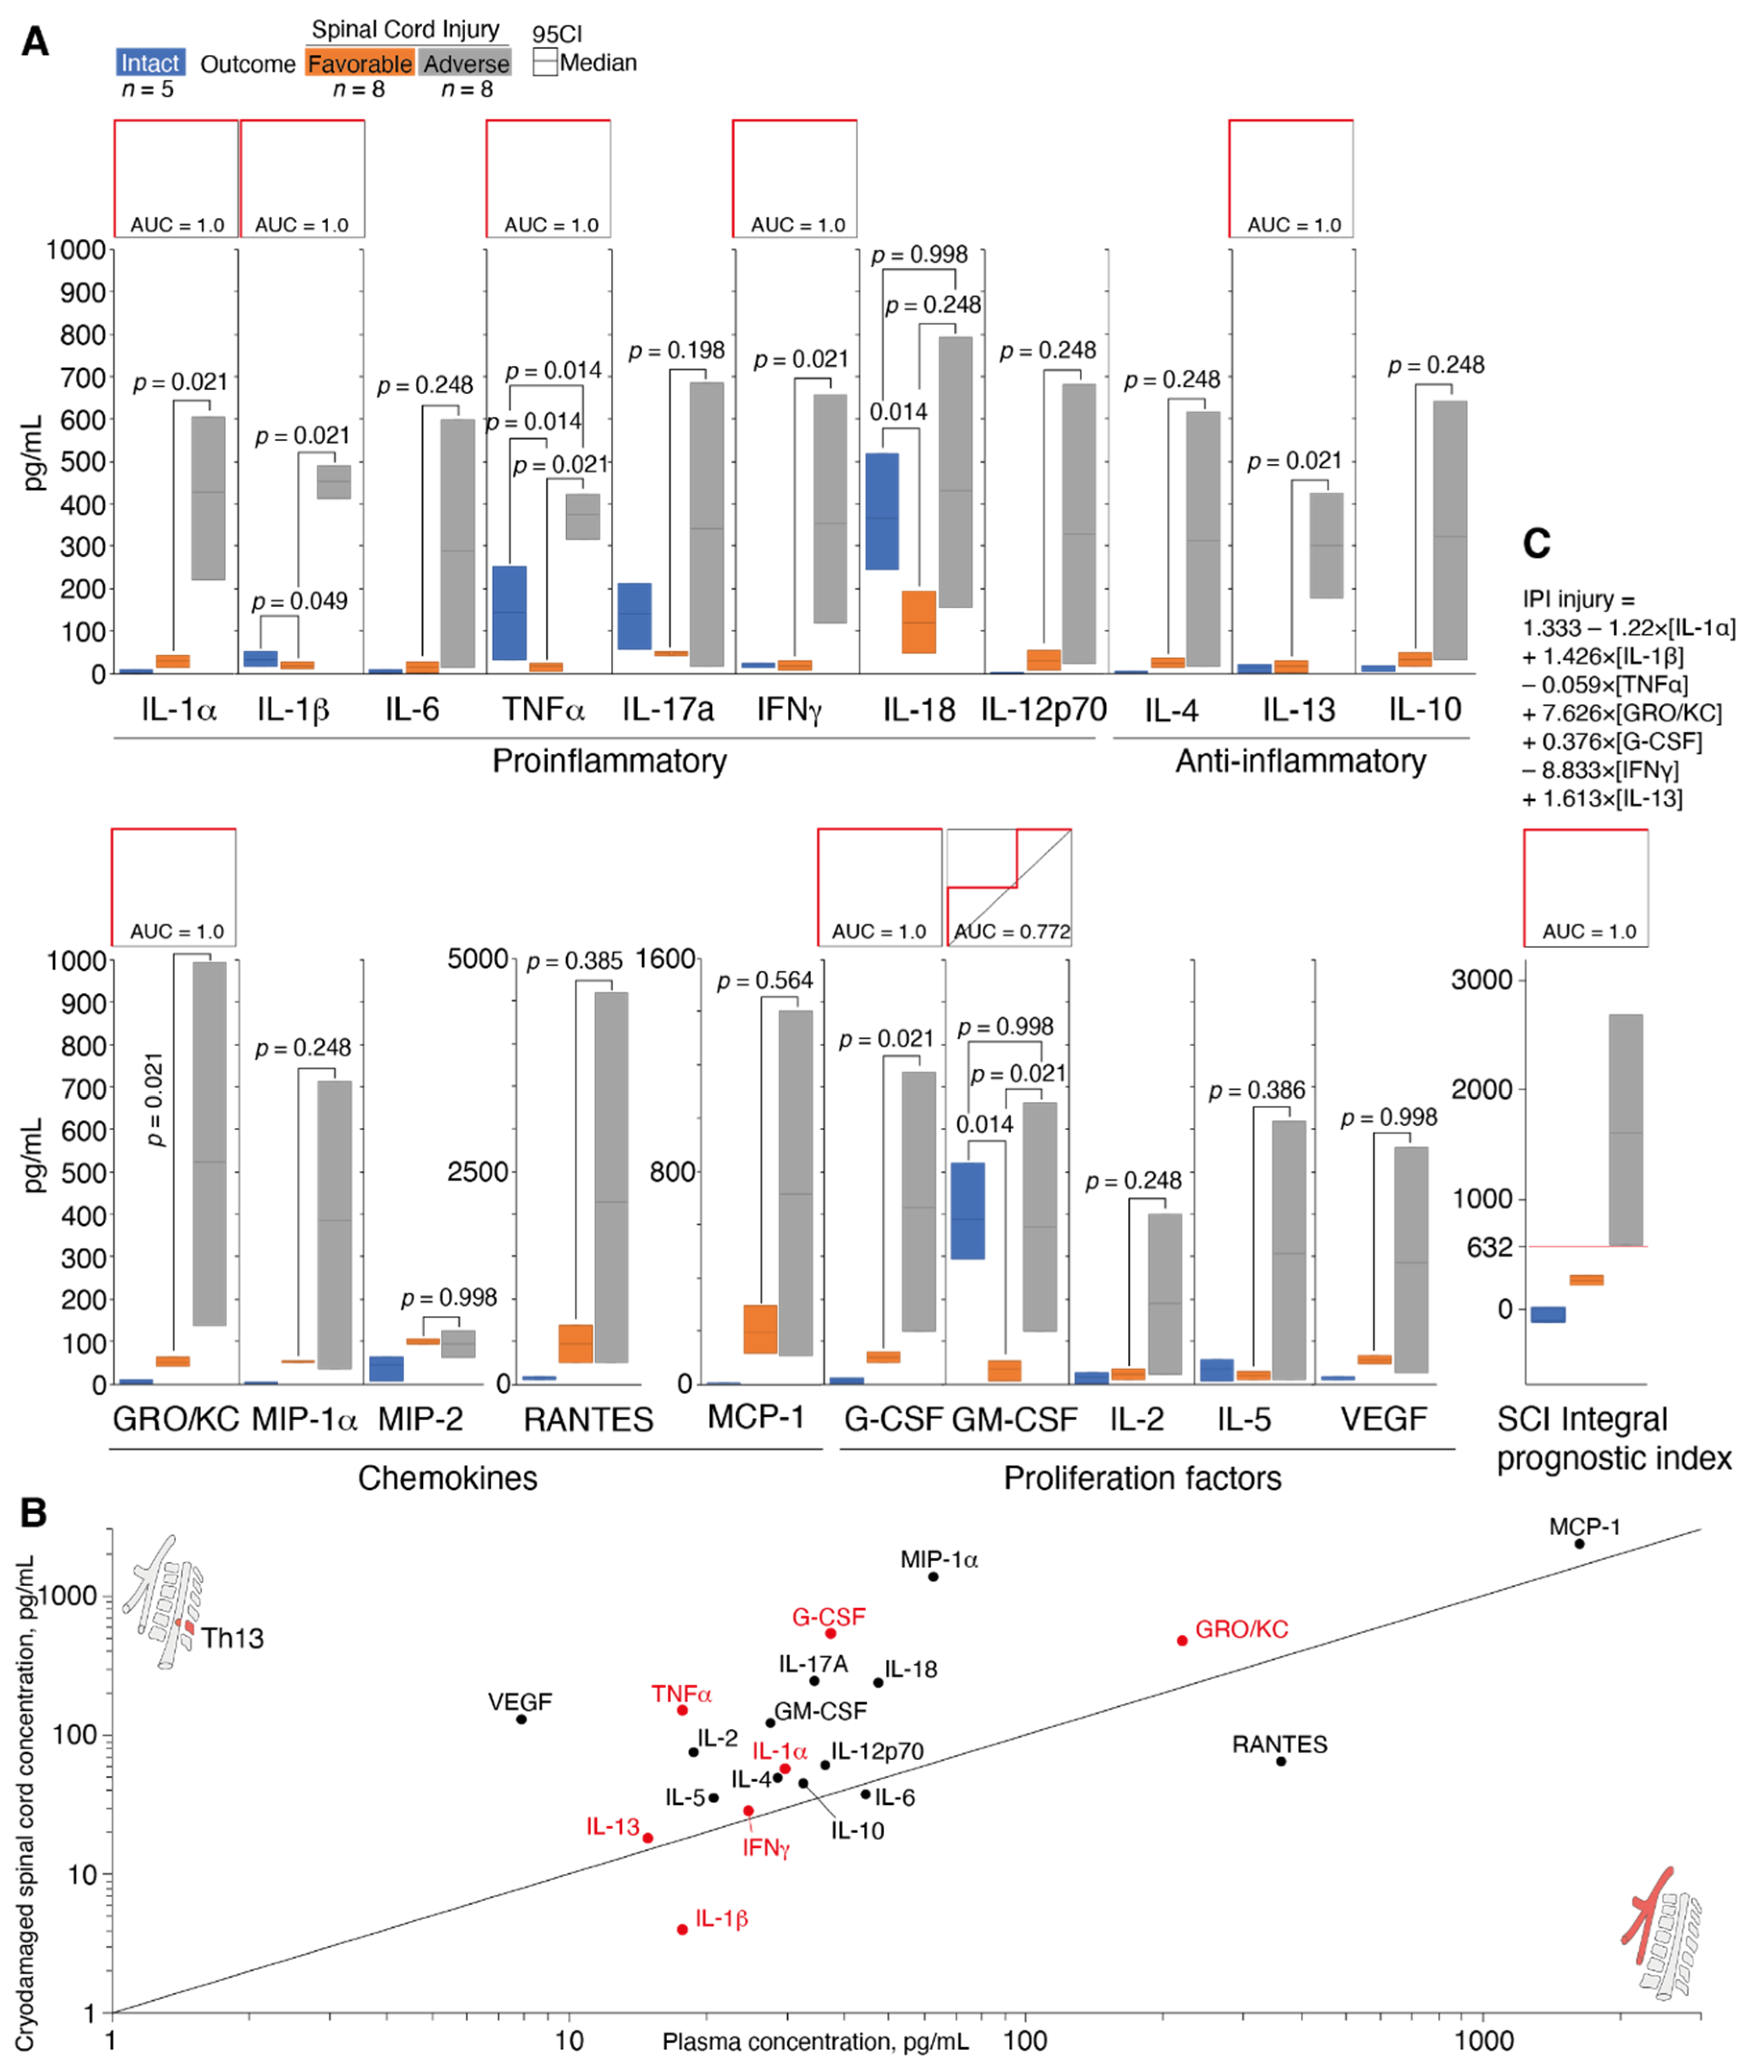

3.4. Determination of Cytokine Status during Spinal Cord Cryoinjury